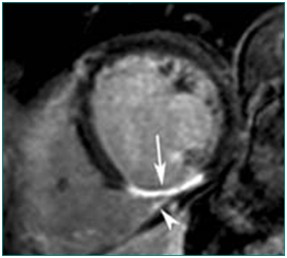

影像科特色检查:心脏磁共振检查

心肌灌注(病例-心肌梗死)